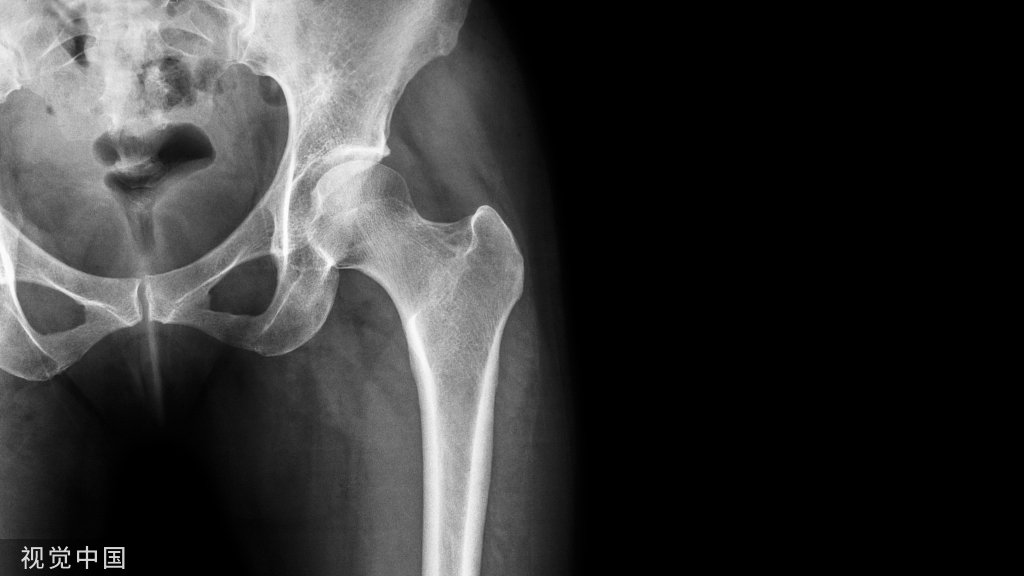

累及后关节面的跟骨骨折需采用手术治疗已经达成共识,传统外侧“L”型扩大入路切口手术后切口并发症较多,随着技术的发展,现已发展出经跗骨窦入路、关节镜辅助复位等技术。 考虑跟骨内松质骨结构,并避免对骨膜及软组织血运造成破坏,有学者创新性采用髓内钉治疗跟骨骨折,并做了系列病例报告,取得良好的治疗效果。

由于继发的距下关节病变和后足的形态变化,移位的跟骨关节内骨折非手术治疗通常与不良结局相关。因此,有人认为只有对关节面和跟骨的形状进行解剖学重建才能获得更好的长期效果,大多数外科医生现在都赞成外科治疗。

在很长一段时间内,治疗跟骨关节内骨折的金标准是通过扩大外侧入路进行切开复位内固定。然而,这种方法经常与伤口愈合并发症(5.8%-43%)相关,包括血肿、伤口浅表坏死、浅表和深部伤口感染。为了降低这些风险,在过去几年内,微创技术得到了很好的发展,包括经皮螺钉固定、经跗骨窦入路、有限后路和关节镜辅助固定。经跗骨窦入路可直接控制关节复位,无需广泛的软组织解剖,并结合经皮内固定,使软组织并发症发生率较低。在这项研究中,我们旨在评估经跗骨窦入路经皮螺钉固定移位的跟骨关节内骨折的疗效。